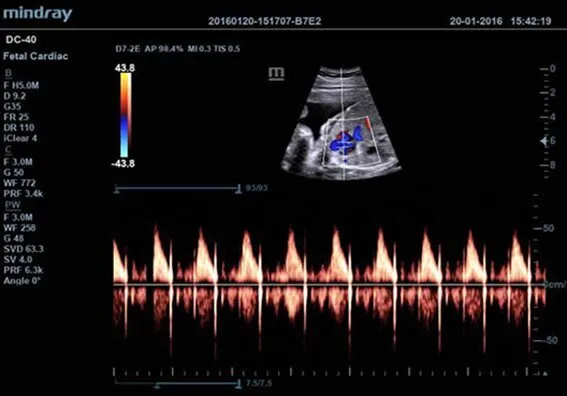

Клинические изображения

| D7-2E | Конвексный датчик объёмного сканирования в реальном масштабе времени для абдоминальных и акушерско-гинекологических исследований (необходим модуль 4D). Уменьшенные габариты и вес |